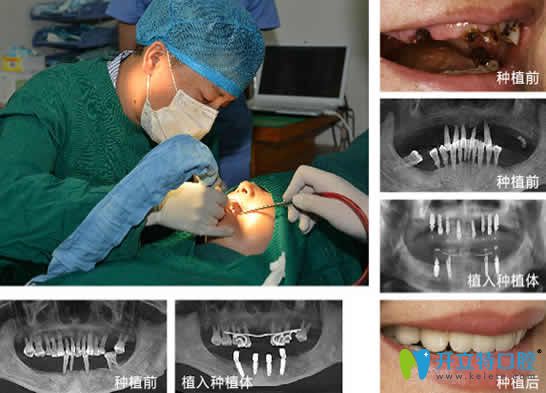

口腔全慶波醫(yī)生種植牙案例效果及顧客評(píng)論:

全醫(yī)生掌握了“4D”種植牙核心技術(shù),種植牙整體水平的很高,整個(gè)手術(shù)過程中無痛,種植后效果也很好。

<!--<i data=20240703-sp></i>-->口腔全慶波種植牙案例效果圖